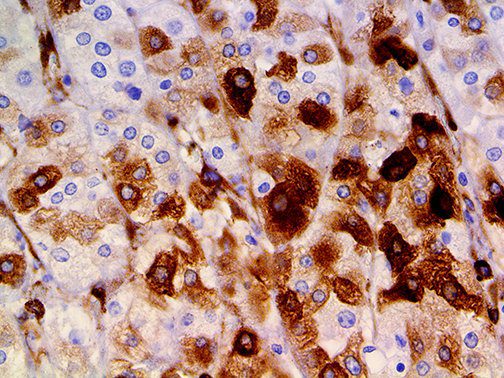

The first cytokines released are interleukin 1β (IL-1β) and tumor necrosis factor-α (TNF-α), which attract a variety of circulating white blood cells (WBCs) to the infection site, including neutrophils, monocytes, macrophages, and natural killer (NK) cells. This response, along with the antipathogenic chemicals released by these cells (i.e., complement), comprise the innate immune response. These cells directly attack the invading pathogen and also release additional cytokines, chief among them interleukin-1 and 6 (IL-6). IL-6 is essential for invoking the adaptive immune response, which calls T-cells, B-cells, and T helper (Th) cells to the infection site. IL-6 also stimulates further recruitment, proliferation and activation of macrophages.

This activation induces inflammatory monocytes to highly express IL-6, starting a localized and then systemic cascade effect that results in hyperproduction of IL-6, which accelerates the inflammatory process. Because IL-6 also increases vascular permeability, excessive levels cause blood vessels to become very leaky. This, along with clotting factors released from vascular endothelial cells, stimulates the coagulation cascade, resulting in microthrombosis (tiny clots), which leads to ischemia and tissue death of the kidney, intestines, heart, liver, brain and extremities.